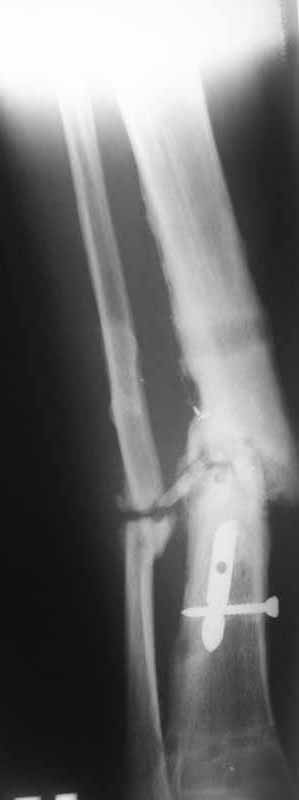

Первично у пациента травма в марте 2009г, когда в результате ДТП получил открытый оскольчатый перелом обеих костей правой голени на границе средней и нижней трети. При поступлении - скелетное вытяжение, затем по заживлению раны произведен остеосинтез пластиной. Со временем (точное время сказать затрудняется) пациенту разрешили полную нагрузку на конечность. Через год после операции пластина сломалась, в связи с чем пластина удалена и установлен интрамедуллярный гвоздь. Через 2 месяца разрешили полную нагрузку и гвоздь сломался. В сентябре 2010 произведено наложение спицевого компрессионно-дистракционного аппарата. В мае 2011 появилось отделяемое в местах проведения спиц, в связи с чем аппарат демонтирован. Правая голень временно иммобилизирована гипсовой повязкой, разрешена нагрузка на правую нижнюю конечность. После снятия повязки - клиника ложного сустава обеих костей правой голени. В настоящее время отмечается угловая деформация правой голени на границе средней и нижней трети с отклонением оси в медиальную сторону. Кожные покровы изменены за счет трофических нарушений(имеют более темную окраску по сравнению со здоровой ногой)На коже рубцы на месте проведения спиц.Движения в коленном и голеностопном суставах в полном объеме безболезненны. Пульсация артерий на стопе отчетливая, выпадение чувствительности от третьего луча в латеральную сторону по тылу стопы.  В таком виде пациент оказался у нас. Рады выслушать предложения о тактике лечения.

Вложение не в текстовом формате было извлечено…

Url     : http://weborto.net:8080/pipermail/ortho/attachments/20110816/e165342b/attachment-0004.jpg